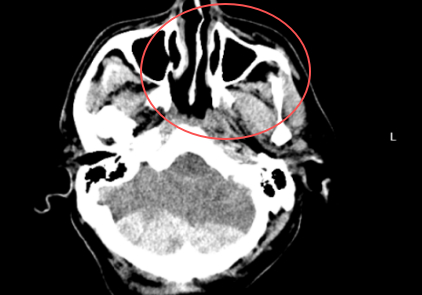

近日,55歲的何先生(化名)在騎三輪車時不慎摔倒,頭部遭受嚴重撞擊,被緊急送至我院急診。當時患者情況十分危急,檢查顯示其顱內(nèi)存在多處出血及骨折,生命危在旦夕。面對這場突如其來的生命危機,醫(yī)院立即啟動急危重癥救治綠色通道。神經(jīng)外科、麻醉科、手術室等多科室迅速響應,在第一時間組成救治團隊。經(jīng)過緊急會診和全面評估,醫(yī)療團隊當機立斷,決定立即為患者實施急診開顱手術。圖片有可能引起不適,慎點圖片有可能引起不適,慎點無影燈下,主刀醫(yī)生趙堅柱憑借豐富的經(jīng)驗和精湛的技術,小心翼翼地清除血腫,2025-10-18

近日,紹興袍江醫(yī)院急診科緊急接收了一名由120轉(zhuǎn)運來的意識不清危重患者。經(jīng)快速檢查,患者被確診為創(chuàng)傷性枕部跨竇硬膜外血腫、創(chuàng)傷性蛛網(wǎng)膜下腔出血、左側(cè)額顳部硬膜下血腫,同時合并全身多處損傷,病情危急。罕見“對沖傷”疊加小腦創(chuàng)傷,病情半小時內(nèi)急轉(zhuǎn)直下該患者所受損傷為顱腦“對沖傷”,即頭部前后方同時受力受損,是多發(fā)傷中的常見類型。更棘手的是,患者合并小腦創(chuàng)傷——這一創(chuàng)傷類型在所有顱腦創(chuàng)傷中占比僅2%-5%,臨床處理難度極大。圖片有可能引起不適,慎點患者入院后病情迅速惡化,半小時內(nèi)即2025-10-07